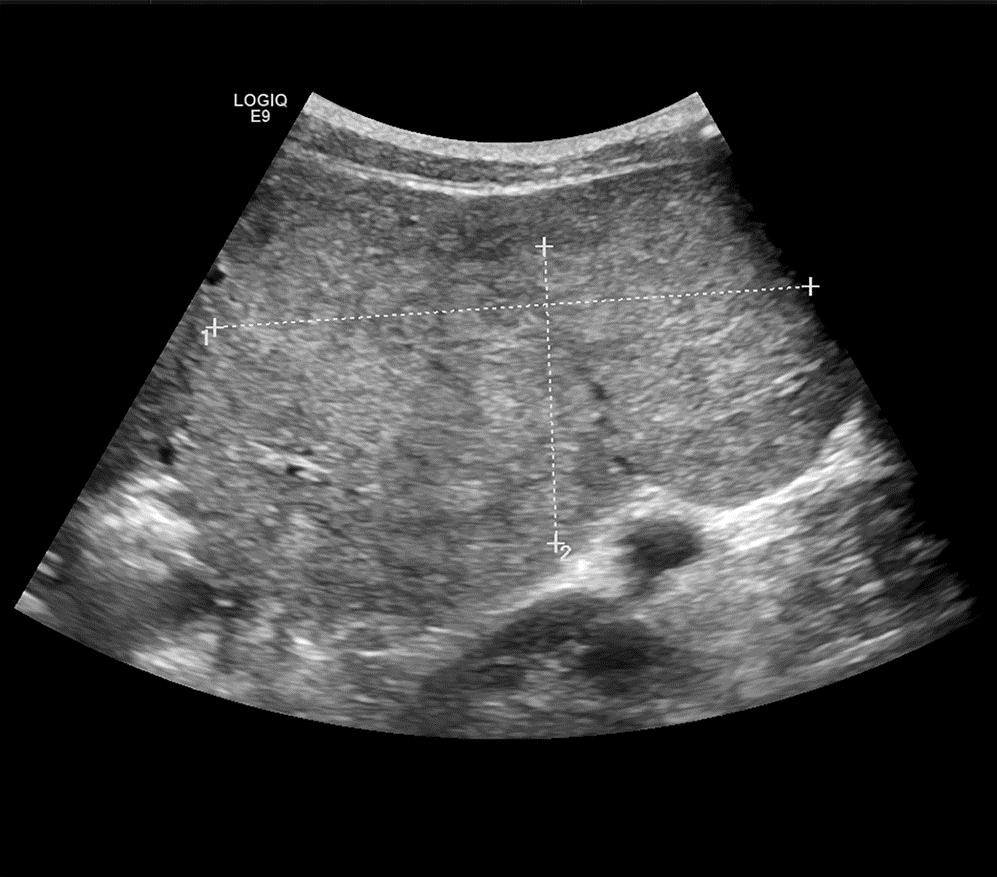

Giant focal nodular hyperplasia of the liver in children: A case report